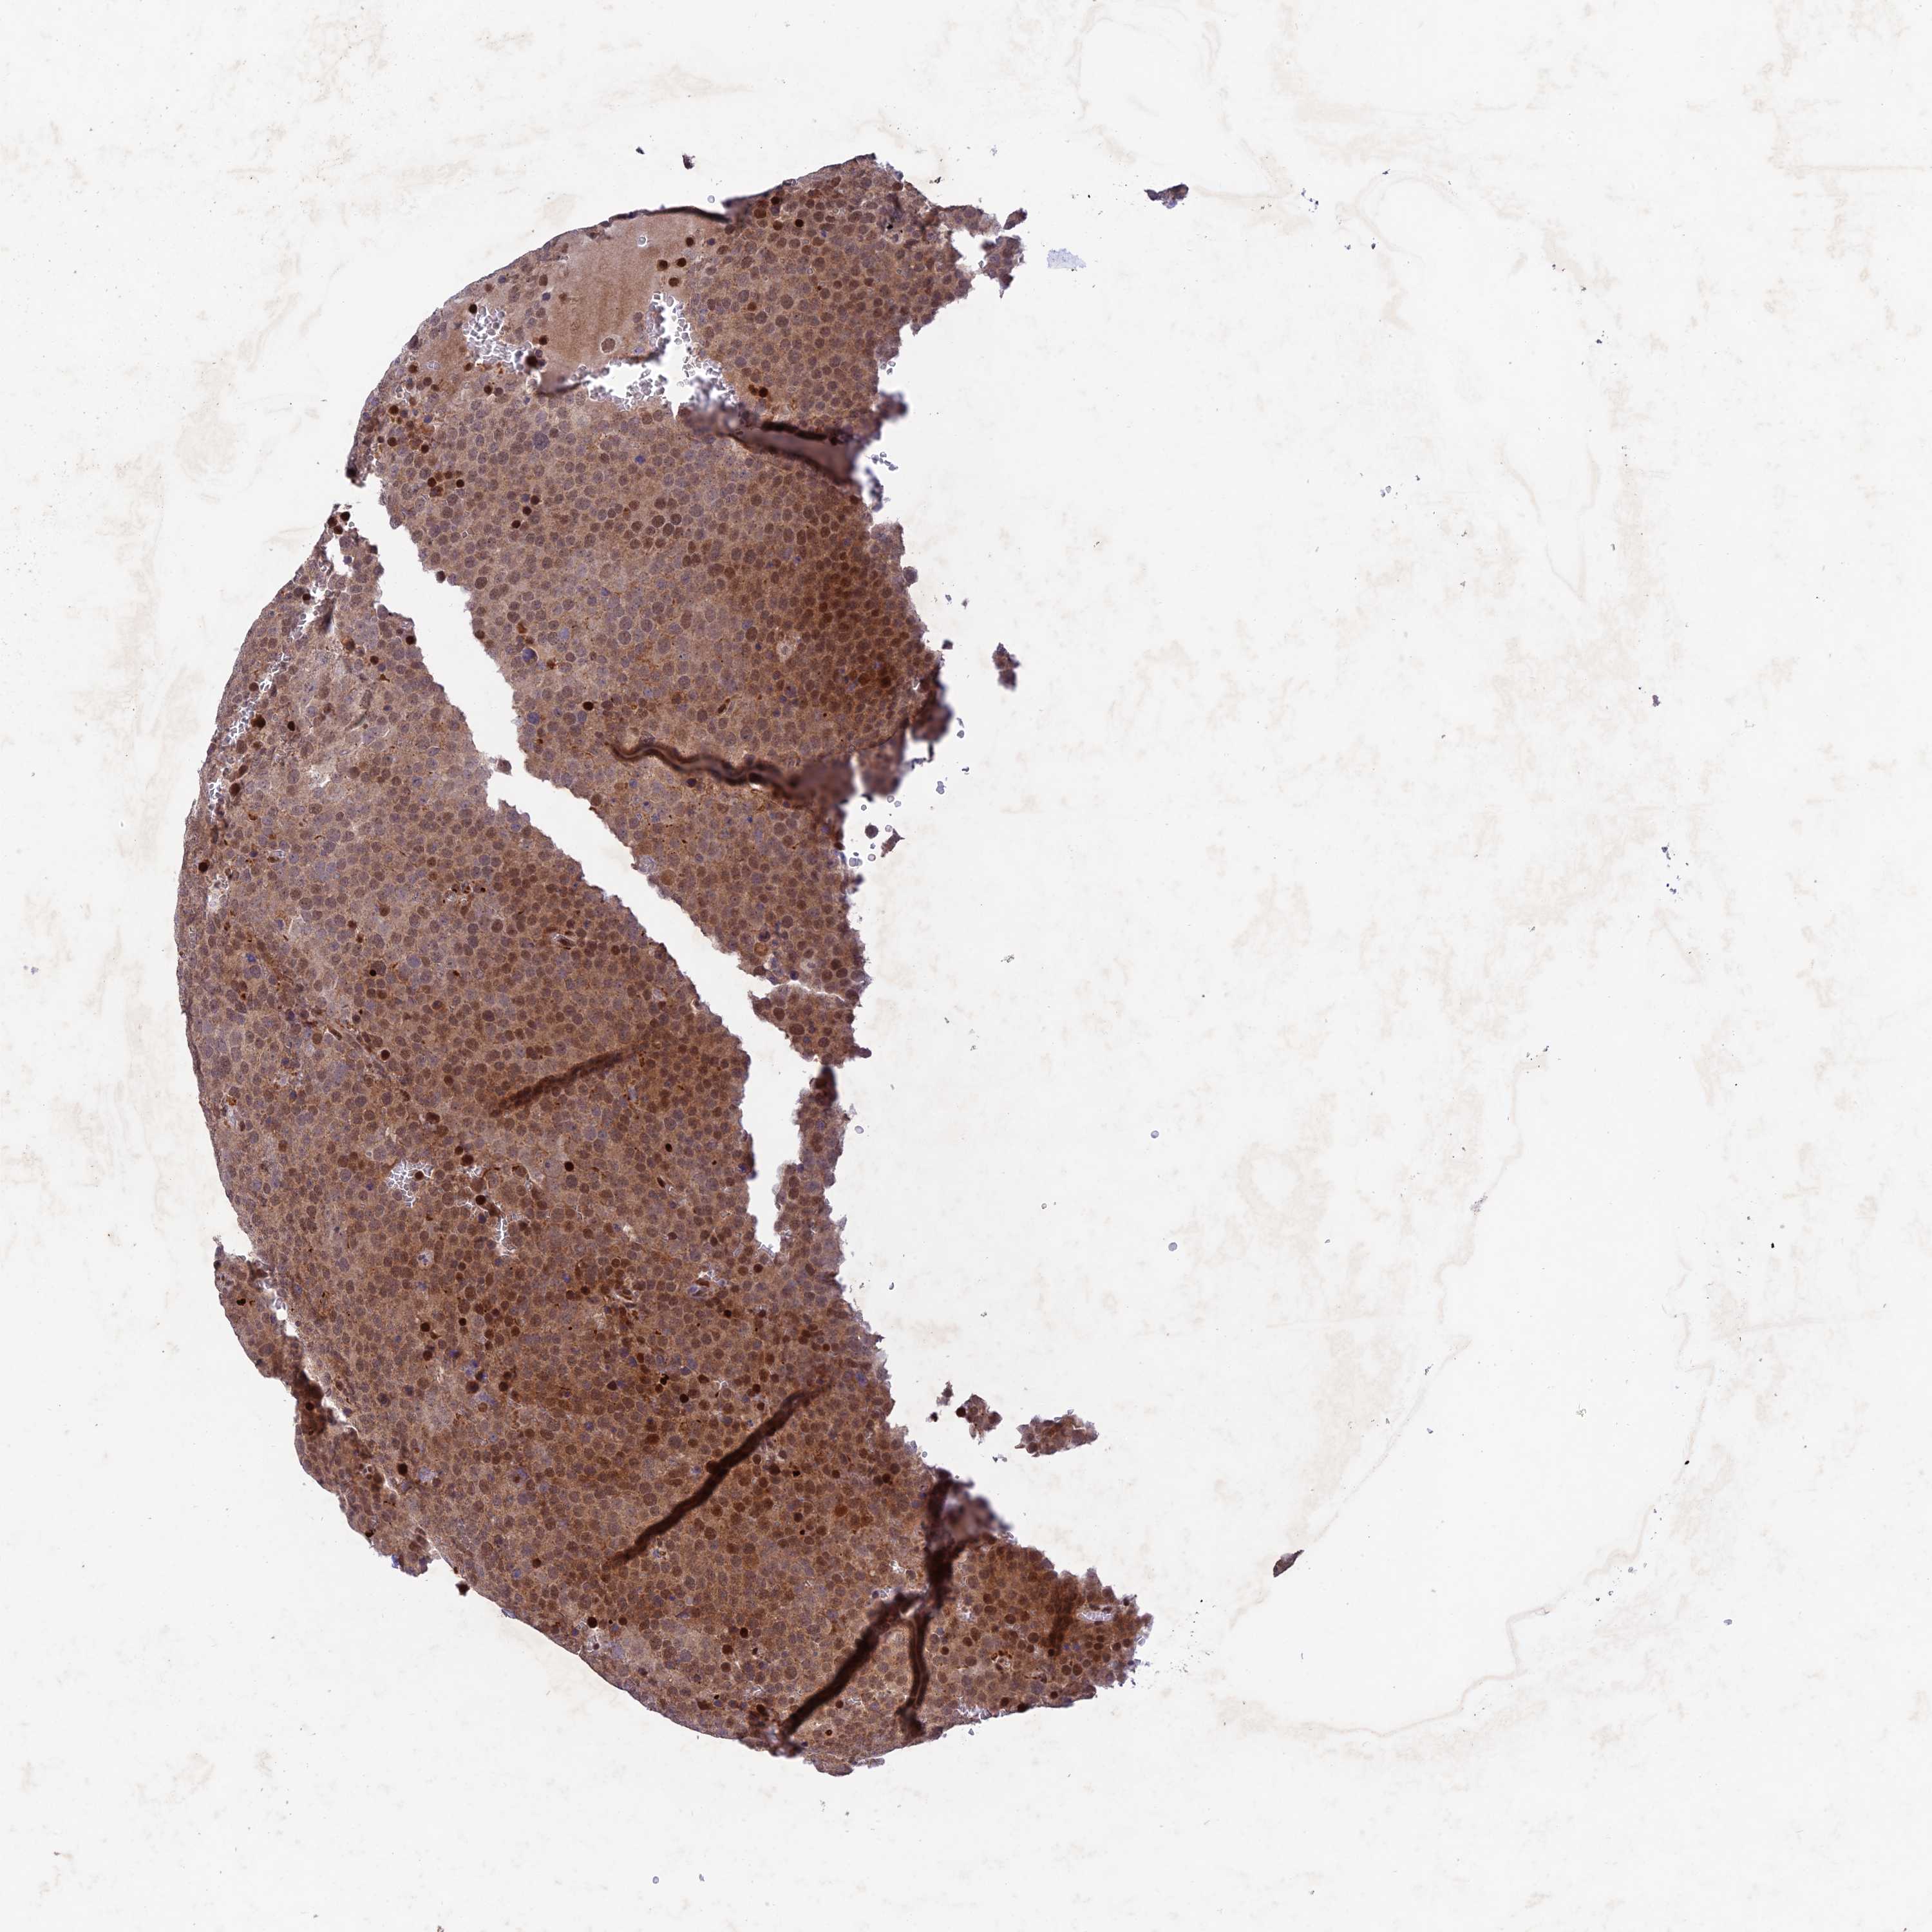

TESTIS CANCER - Protein expressioni

A mouse-over function shows sample information and annotation data. Click on an image to view it in a full screen mode. Samples can be filtered based on level of antibody staining by selecting one or several of the following categories: high, medium, low and not detected. The assay and annotation is described here.

Note that samples used for immunohistochemistry by the Human Protein Atlas do not correspond to samples in the TCGA dataset.

Antibody stainingi

Antibody staining in the annotated cell types in the current human tissue is reported as not detected, low, medium, or high, based on conventional immunohistochemistry profiling in selected tissues. This score is based on the combination of the staining intensity and fraction of stained cells.

Each image is clickable and will lead to virtual microscopy that enables deeper exploration of all samples and also displays staining intensity scores, fraction scores and subcellular localization as well as patient and tissue information for each sample.

Antibody HPA043470

Antibody HPA048143

Staining

High

Medium

Low

Not detected

Intensity

Strong

Moderate

Weak

Negative

Quantity

>75%

75%-25%

<25%

None

Location

Nuclear

Cytoplasmic/membranous

Cytoplasmic/membranous,nuclear

Carcinoma, Embryonal, NOS

Seminoma, NOS